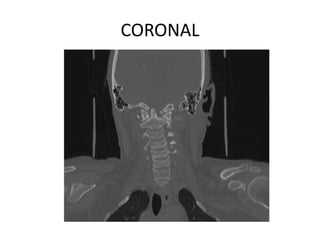

M Ramanamma is a 48-year-old female who presented with neck pain and paresthesias in her limbs for the past 5 months. On examination, she had decreased strength in her right upper and lower limbs and hypertonia in her lower limbs. Imaging showed atlantoaxial dislocation with compression of the cervical spinal cord at C1-C2, explaining her symptoms.